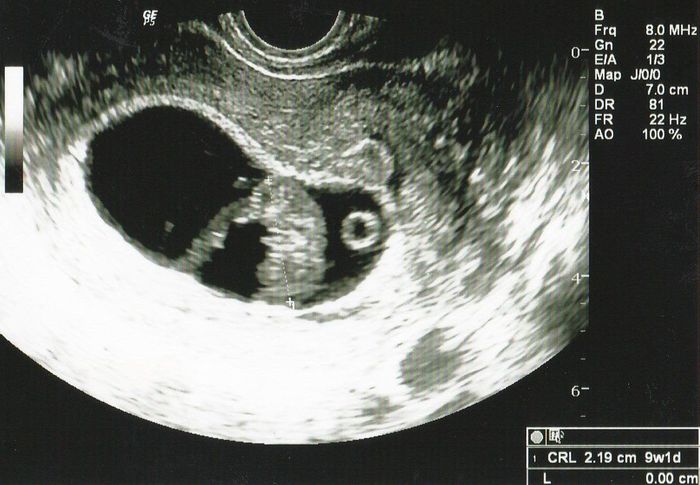

妊娠8週目のエコー写真 頭と足が確認でき「おぉ~」と心の中で叫ぶ

CRL=2.19cm

頭を下に向け、背中を丸めた赤ちゃんが映し出され、ただ、ただ驚くばかり。夫とは「本当にここ(おなか)にいるんだね」と、やっぱりちょっと他人事のような気持ちでした。今このエコー画像を見ると「かわいい~」と思えるのですが、当時は宇宙人を見ている感覚でした。つわりは軽度でしたが、とにかく眠く、仕事の合間をみて昼寝をして、しのいでいました。食欲も落ち、体重が1kg位減りました。